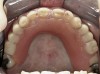

Initial examination revealed a partial edentulous patient with extensive wear of the maxillary anterior teeth and moderate wear in the mandibular teeth (Figure 1, Figure 2, Figure 3 , Figure 4, Figure 5, Figure 6 and Figure 7). The patient's maxillary and mandibular RPDs also showed excessive wear and multiple signs of fractures (Figure 2 and Figure 3). The patient had been wearing a mandibular nightguard for 8 years.

Figure 4  Intraoral occlusal view of maxillary dentition presenting excessive signs of wear.

Figure 4